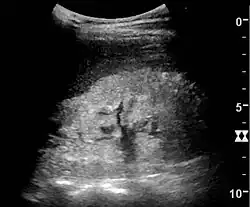

Illustration of a kidney from a person with chronic renal failure

Ultrasound

Kidney ultrasonography is useful for diagnostic and prognostic purposes in chronic kidney disease. Whether the underlying pathologic change is glomerular sclerosis, tubular atrophy, interstitial fibrosis, or inflammation, the result is often increased echogenicity of the cortex. The echogenicity of the kidney should be related to the echogenicity of the liver or the spleen. Moreover, decreased kidney size and cortical thinning are often seen, especially when the disease progresses. However, kidney size correlates to height, and short persons tend to have small kidneys; thus, kidney size as the only parameter is unreliable.[63]